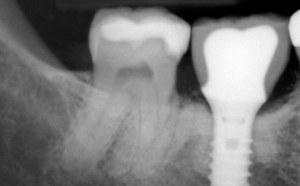

임플란트는 3가지 종류로 구성되어 있습니다. 픽스쳐 – 어버트먼트 – 상부구조물 입니다. 여기서 당연히 크라운(상부구조물)이 무엇이냐에 따라서도 가격이 달라질 수 있는데요. 본인에게 맞는 크라운별 가격과 특징은 하기를 참고하시길 바랍니다.

오늘은 픽스쳐, 즉 임플란트의 종류만에 대한 가격과 특징들에 대해 알아보도록 하겠습니다.

어금니 임플란트 종류